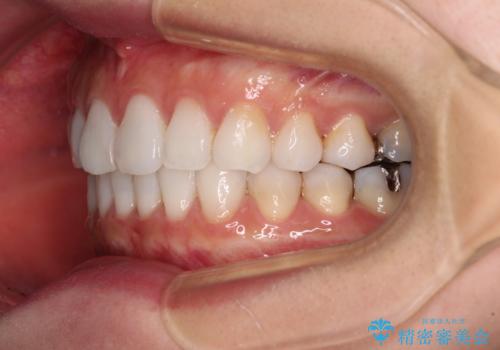

- 前歯のデコボコを気にして来院された患者様です。

海外に留学をされており、卒業後はしばらく日本にいるものの、再び就職のため出国するとのことでした。

定期的に日本に戻ってくる予定であるため、来院頻度の少ないインビザラインにて矯正治療を行うこととしました。

歯列不正が軽度であり、インビザラインの装着時間を遵守してくださったため、日本と海外を行き来しながらも2年弱でしっかりと仕上げることができました。